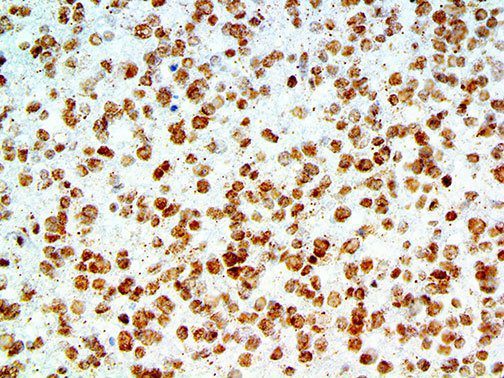

It is the ICU physician who is most likely to witness one of the deadliest manifestations of the abnormal immunological response, the cytokine storm syndrome (CSS). This response is also referred to by some as the cytokine release syndrome (CRS). CSS is characterized by continuous activation and expansion of macrophage and lymphocyte populations, which secrete large amounts of cytokines, causing the cytokine storm. This massive cytokine release is akin to hemophagocytic lymphohistiocytosis (HLH) disease, a syndrome characterized by initial unchecked and persistent activation of cytotoxic T lymphocytes and NK cells.

Clinical and laboratory manifestations of HLH include fever, enlarged liver and/or spleen, neurologic dysfunction, coagulopathy, liver dysfunction, cytopenias (i.e., low levels of erythrocytes, leukocytes, and/or platelets), hypertriglyceridemia, hyperferritinemia, hemophagocytosis, and eventually diminished NK cell activity as the immune system becomes progressively paralyzed. HLH can be familial (primary HLH) or secondary to another disease process (sHLH), such as rheumatic disease, in which it is referred to as macrophage activation syndrome (MAS, characterized by elevated ferritin).